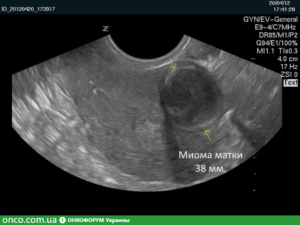

При обращении пациентки с жалобами проводится ультразвуковое обследование, сдаются соответствующие анализы. УЗИ является самым точным выявлением данного заболевания, а также срока его появления.

Раньше степень развития болезни соотносили с неделями беременности, исходя из того насколько сильно увеличена матка пациентки. Это повелось со времен, когда отсутствовала УЗИ-диагностика. Сейчас определение типа “миома, соответствующая 8-9 неделе беременности” служит маркером величины миомы, но не диагностическим критерием.

Достоверно диагностировать заболевание можно только по результатам ультразвукового исследования. Ультразвуковая визуализация позволяет точно определить размер узлов, их расположение и тип. Необходимо, чтобы при оформлении результата врач-узист сделал не только описание узлов, но и схематический рисунок матки с их расположением и указанием размера каждого.

Размеры миомы, как было сказано выше, акушерами-гинекологами сопоставляется с размером тела матки на определенном сроке беременности. Во время ультразвукового исследования можно измерить новообразование в сантиметрах.

Подобное исследование матки демонстрирует увеличение органа, а также саму миому (большого и небольшого размера).Миому может быть выявлена уже на самых начальных стадиях, когда ее диаметр меньше 1 сантиметра, не говоря уже про достаточно большие узлы миомы матки 7-8 недель и больше.